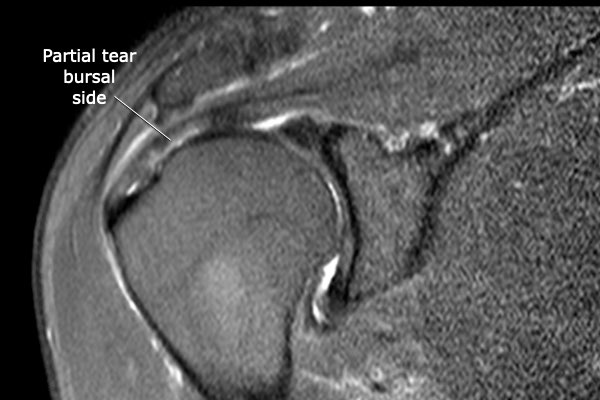

Trên chuỗi xung T2W có một tổn thương rách mặt túi hoạt dịch kích thước lớn.

Lưu ý rằng trên MRI khớp có thuốc tương phản từ, tổn thương rách không quan sát thấy do thuốc tương phản từ nội khớp không thể tiếp cận vị trí khuyết trong gân.